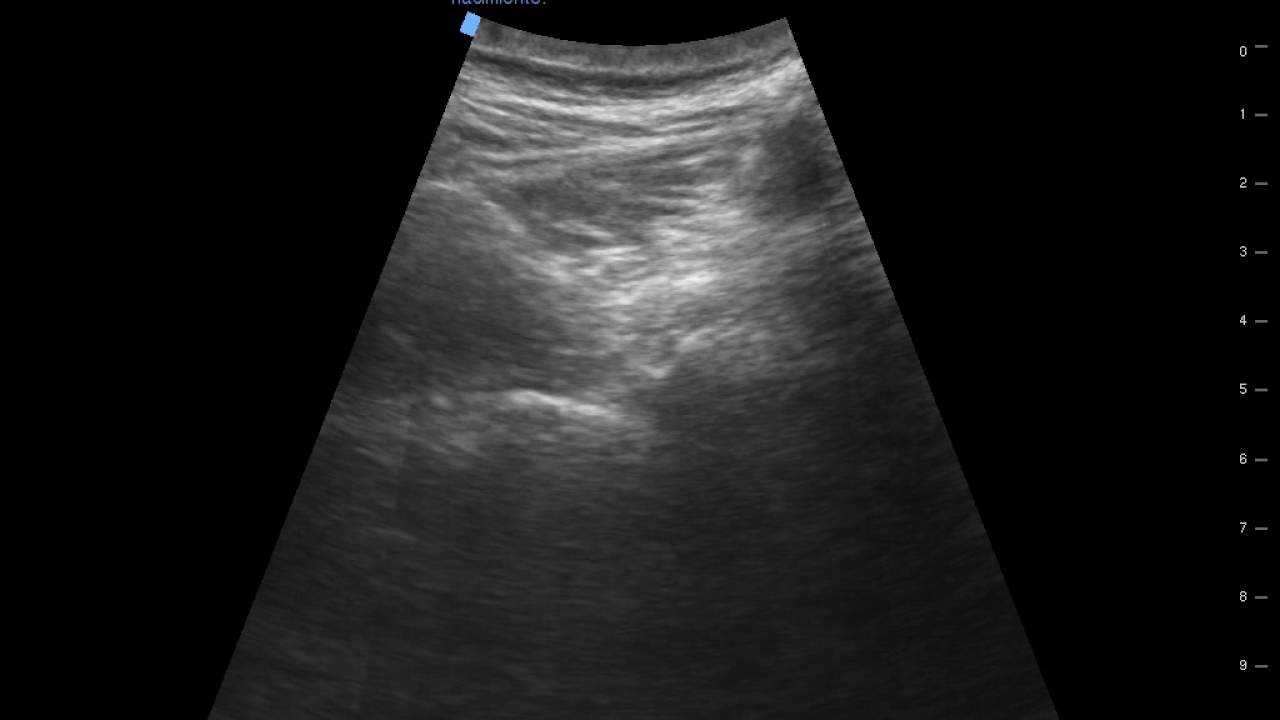

Bloqueo Radicular Lumbar Ecoguiado

Автор: Victor I. Espinoza A. CLINICA DEL DOLOR DE LIMA

Описание: Paciente con dolor radicular post laminectomia buena respuesta , presenta hernia recidivada vs fibrosis en espera de probable turno quirurgico , no responde al ozono paravertebral y epidural